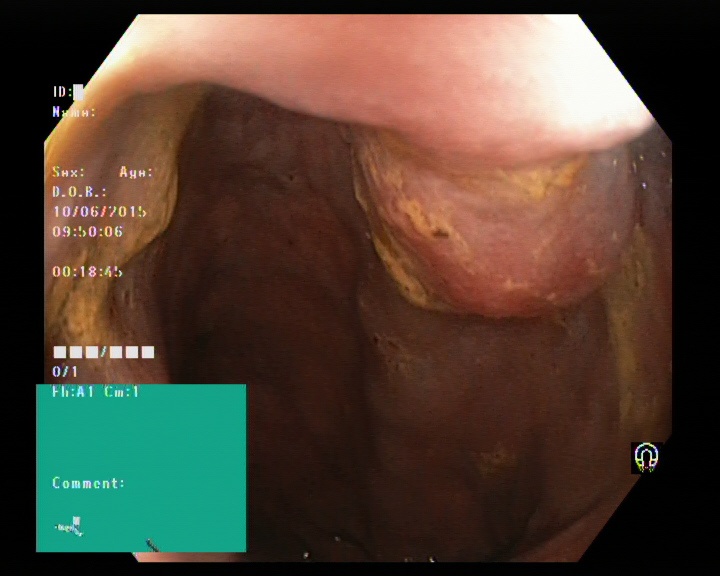

The Kvaris-SEG (Jha et al., 2020c) training dataset can be downloaded from https://datasets.simula.no/kvasir-seg/. It contains 1,000 polyp images and their corresponding ground truth mask as shown in Figure 1. The dataset was collected from real routine clinical examinations at Bærum Hospital in Norway by expert gastroenterologists. The resolution of images varies from to pixels. Some of the images contain a green thumbnail in the lower-left corner of the images showing the scope position marking from the ScopeGuide (Olympus) (see Figure 2). We annotate another separate dataset consisting of 160 new polyp images and use the resulting dataset as the test set to benchmark the participants’ approaches. Figure 2 shows some examples of test images used in the challenge.